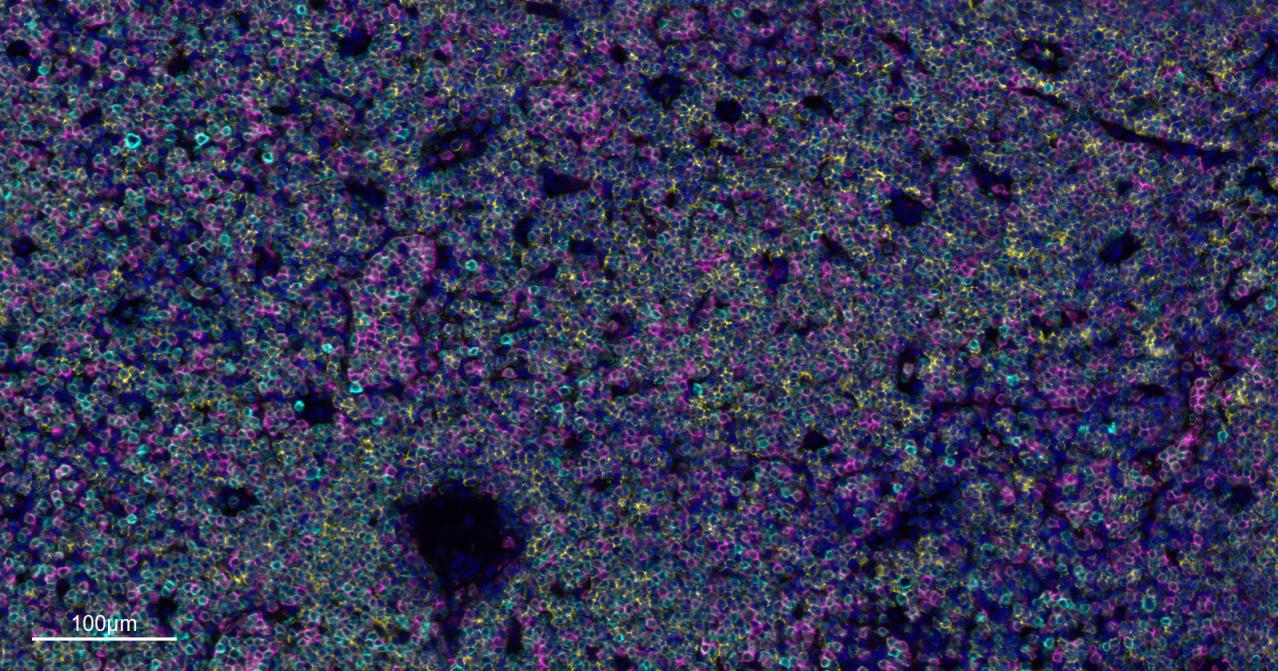

Immunology > Adaptive Immunity > Regulatory T Cells

Immunology > Adaptive Immunity > T Cells > CD

Stem Cells > Hematopoietic Progenitors > Lymphoid > T Lymphocytic Lineage

Stem Cells > Hematopoietic Progenitors > Myeloid > Dendritic Cell Lineage

Stem Cells > Hematopoietic Progenitors > Myeloid > Monocytic Lineage

| mIHC | Human | 1:100-500 |